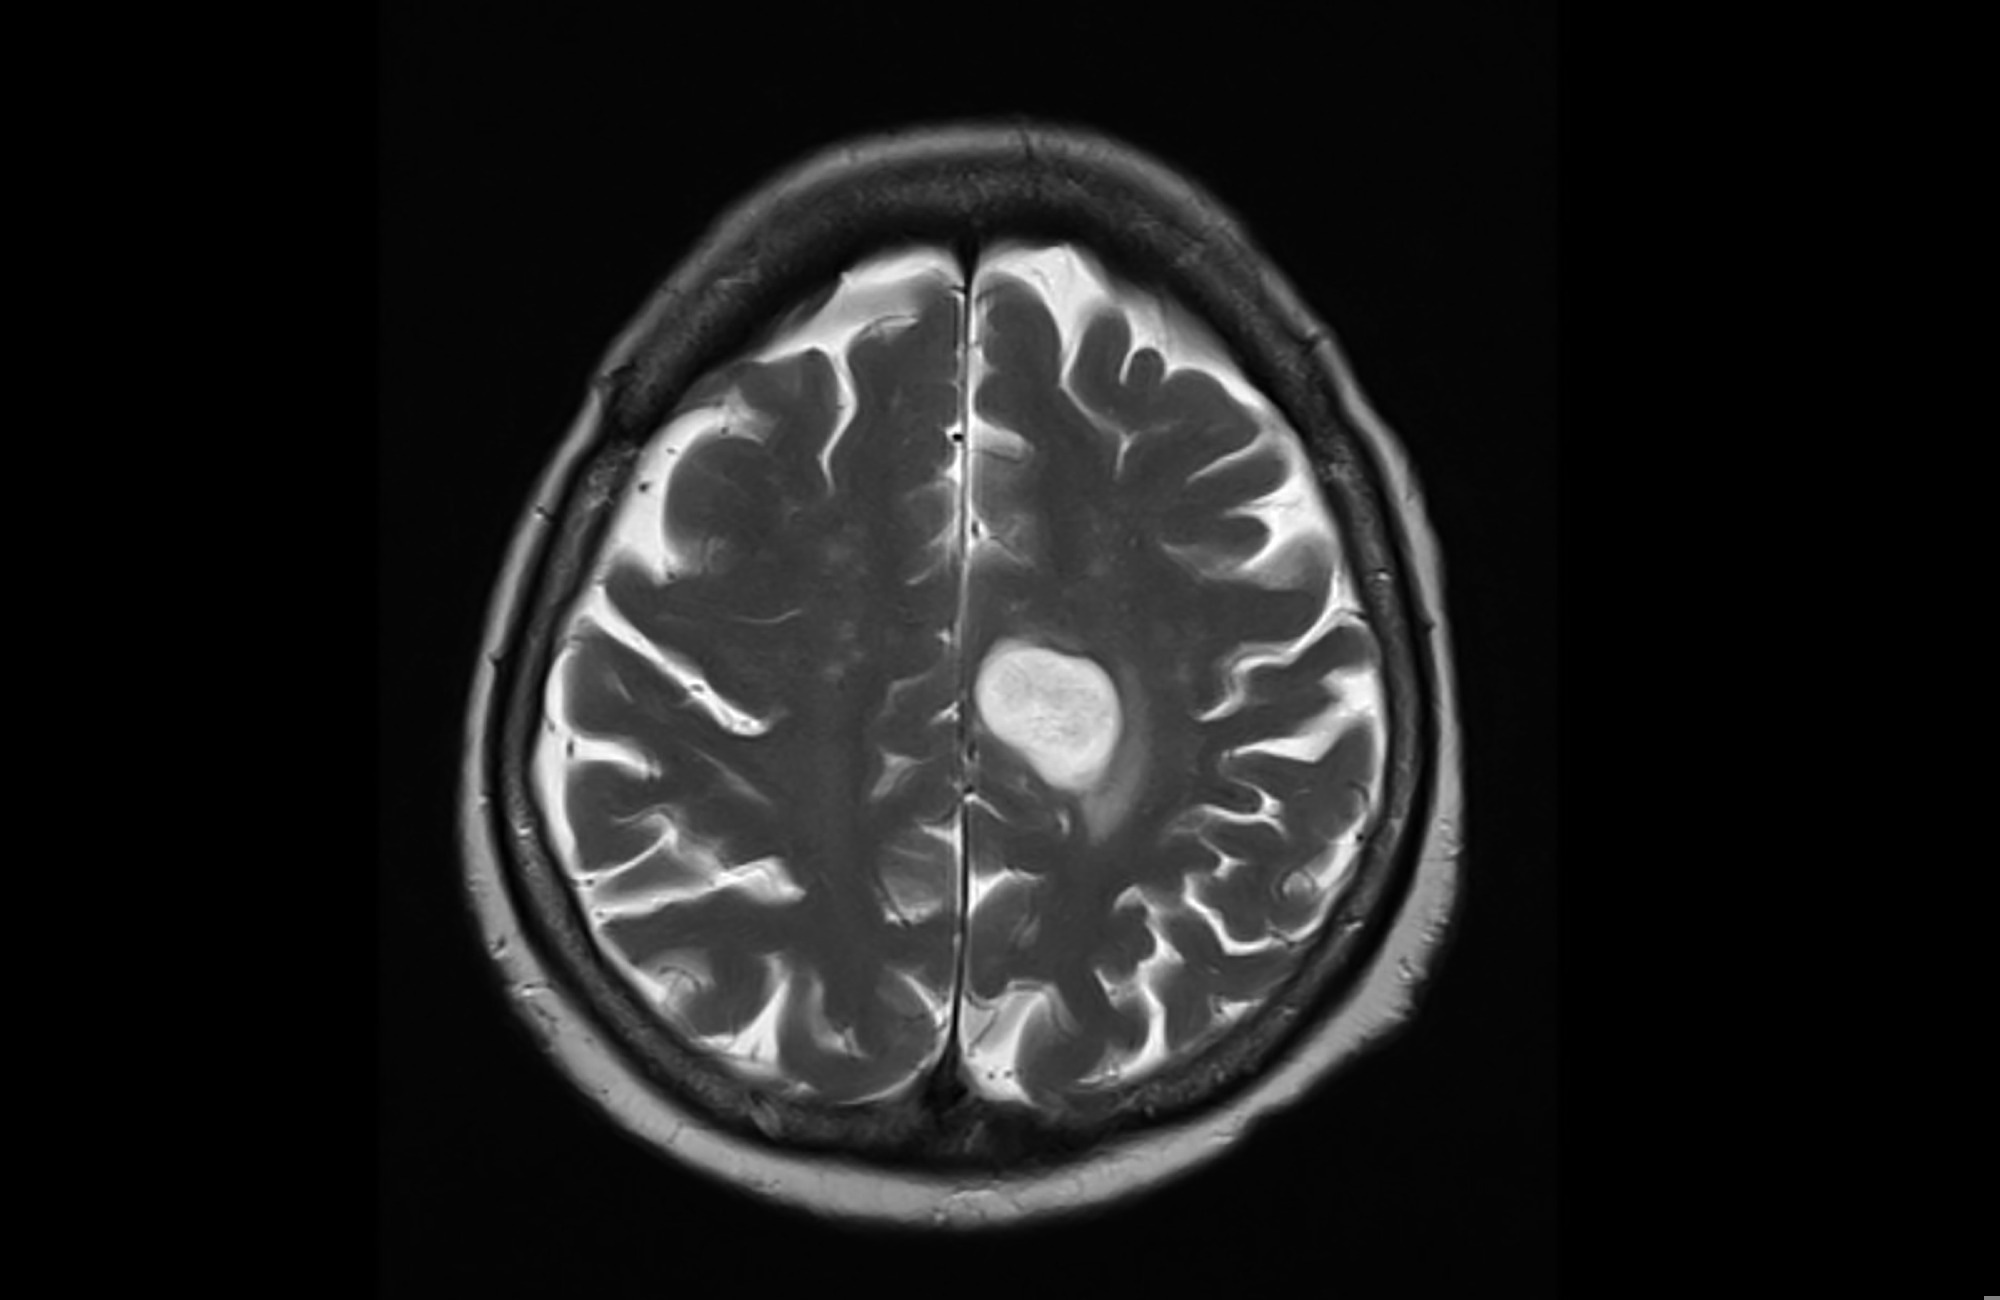

A glioma is a type of brain tumor that arises from glial cells. Based on their aggressiveness, gliomas can be further classified into four grades, with grades I and II considered to be less invasive than grades III and IV.

It remains unclear what environmental or genetic factors can lead to the development of a glioma. Recently, 1,000 gliomas from The Cancer Genome Atlas (TCGA) and Glioma Longitudinal Analysis (GLASS) were analyzed to identify mutational signatures present in these tumors.